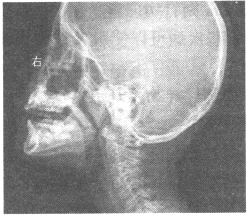

女,5岁,耳鸣,常开口呼吸,睡眠时打鼾,鼻腔分泌物多。X线检查如图所示,最可能的诊断是

女,5岁,耳鸣,常开口呼吸,睡眠时打鼾,鼻腔分泌物多。X线检查如图所示,最可能的诊断是<img border="0" style="width: 251px; he

[单选题]女,5岁,耳鸣,常开口呼吸,睡眠时打鼾,鼻腔分泌物多。X线检查如图所示,最可能的诊断是A.鼻息肉B.扁桃体炎C.腺样体肥大D.鼻炎E.鼻窦炎

[单选题]女,5岁,耳鸣,常开口呼吸,睡眠时打鼾,鼻腔分泌物多。X线检查如图所示,最可能的诊断是()A . 鼻息肉B . 扁桃体炎C . 腺样体肥大D . 鼻炎E . 鼻窦炎